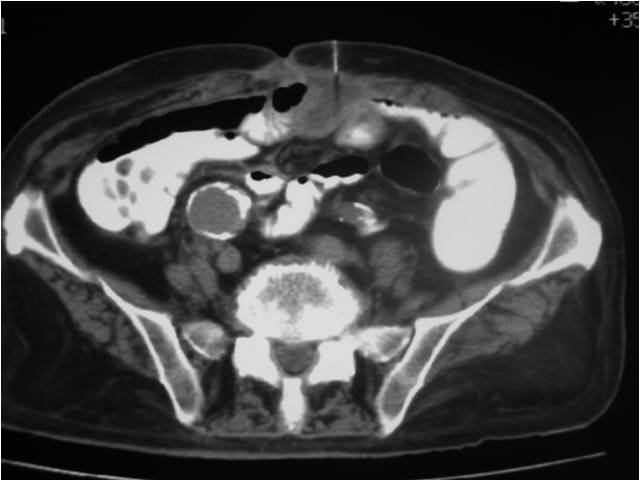

- Abscess post left hemicolectomy

- Successful placement and drainage

- Placement of two sump catheters in a abdominal abscess (surgery of inflammatory bowel disease), displacement of upper one